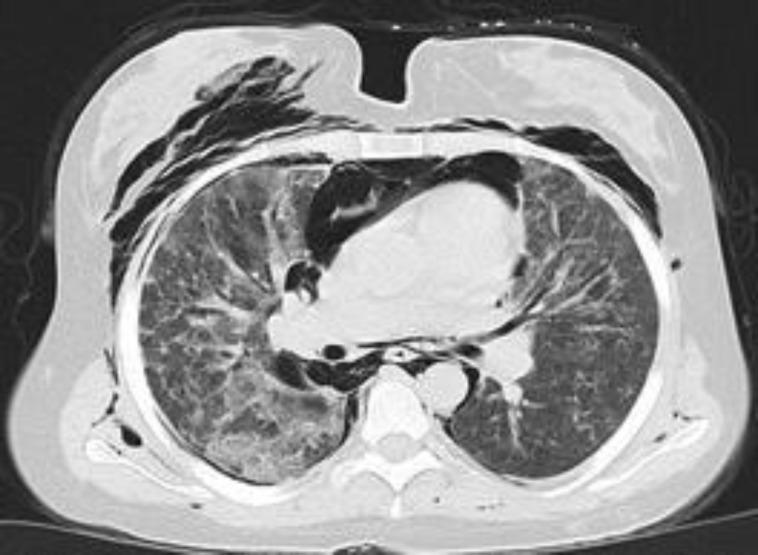

A 20-year-old woman was admitted with neck pain, dyspnea, cough, and fever. She had been diagnosed with dermatomyositis 21 months prior. A thorax computed tomography (CT) scan revealed ground glass opacities in her lungs, pneumomediastinum, pneumothorax, and subcutaneous emphysema. Despite intensive immunosuppressive therapy, clinical deterioration and radiological progression were observed, ultimately the patient died.

一名20岁女性因颈部疼痛、呼吸困难、咳嗽和发热入院。她在21个月前被诊断为皮肌炎。胸部计算机断层扫描(CT)显示其肺部有磨玻璃影、纵隔气肿、气胸和皮下气肿。尽管进行了强化免疫抑制治疗,但仍观察到临床恶化和影像学进展,最终患者死亡。